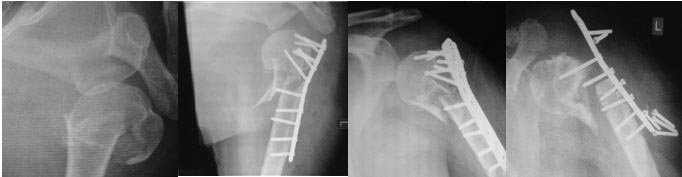

насчет "Изначально репозиция очень даже ничего! " Вы наверное шутите. Насчет репозиции, то очень даже не очень. Остеосинтез еще краше- пластина и винты в суставе. Начали разработку- акромион уперся в верх пластины и имеем то, что имеем. К врачу ЛФК никаких здесь претензий быть не может- разрабатывали на совесть, несмотря на сопротивление металла. Надо переделать остеосинтез, либо пластиной типа Филос, либо БИОС.

Одной проекции маловато для полноценного планирования, но в общих чертах - здесь хорошо бы выполнить закрытый интрамедуллярный остеосинтез современным стержнем для этой локализации.

Multiloc (Synthes) был бы IMHO наилучшим выбором, поскольку позволяет ввести максимальное количество винтов в головку. Но важнее имплантата - это хорошая репозиция. И лучше закрытая. Описание техники представлено здесь.

Пациентке предлагают только эндопротезирование. 7 винтов в головку кости были вкручены в точку. И от головки не осталось какого-то нормального фрагмента.

Извините коллеги травматологи, если ошиблась в терминологии. Но предлагают эндопротезирование,без выбора. Может быть у нас в Новосибирске нет альтернативы.

Все там не так плохо с головкой даже без аугментации. Главное, что цела манжета, то есть все мягкотканые прикрепления сохранены, то есть головка кровоснабжается. Кости там для фиксации специализированного гвоздя, в частности, Multiloc - более чем достаточно. Как сделать - в статье написано. Пусть доктора посмотрят, ничего там особо сложного нет.